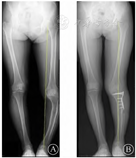

患者,女,51岁,因"左膝疼痛伴活动不利两年余"入院,40年前因左侧胫骨骨髓炎于当地医院行"胫骨开窗引流+死骨去除术"。查体:左膝关节内翻畸形,前内侧可见一长约20 cm陈旧性手术瘢痕(图1、图2) ,肤温肤色正常,浮髌试验(-),磨髌试验(-),内侧间隙压痛(+),外侧间隙压痛(-),Lachman试验(-),旋转挤压试验(+)。左膝ROM: 0°~100°,双下肢肌力、肌张力、末梢血运等均正常。辅助检查: CT示左侧胫骨骨小梁紊乱伴胫骨上段变形;双下肢全长正侧位X线:左膝内翻畸形,关节间隙狭窄,左侧胫骨短缩弯曲。术前美国特种外科医院(HSS)评分为72分,疼痛视觉模拟评分(VAS)为5分。

注: A为左膝内翻畸形,左侧胫骨短缩,内侧干骺端硬化; B为术后力线矫正经过Fujisawa点。